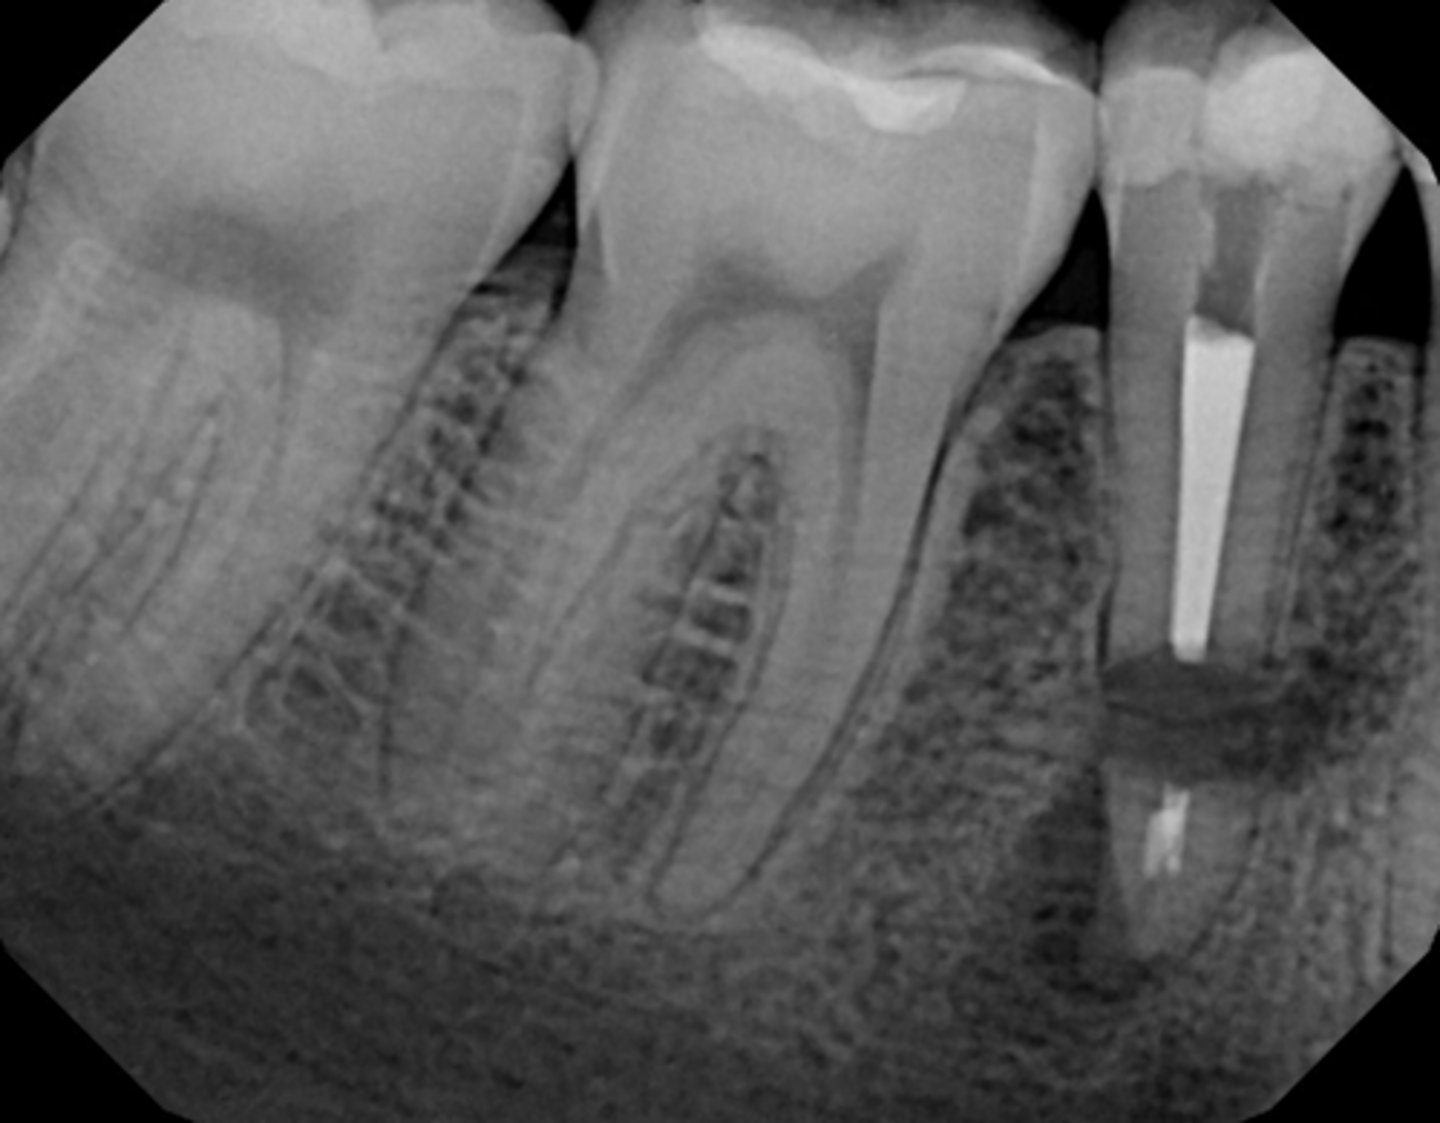

separated instrument

ID the procedural error:

perforation

Post too large

Post too long

Post too large (with apical debris)